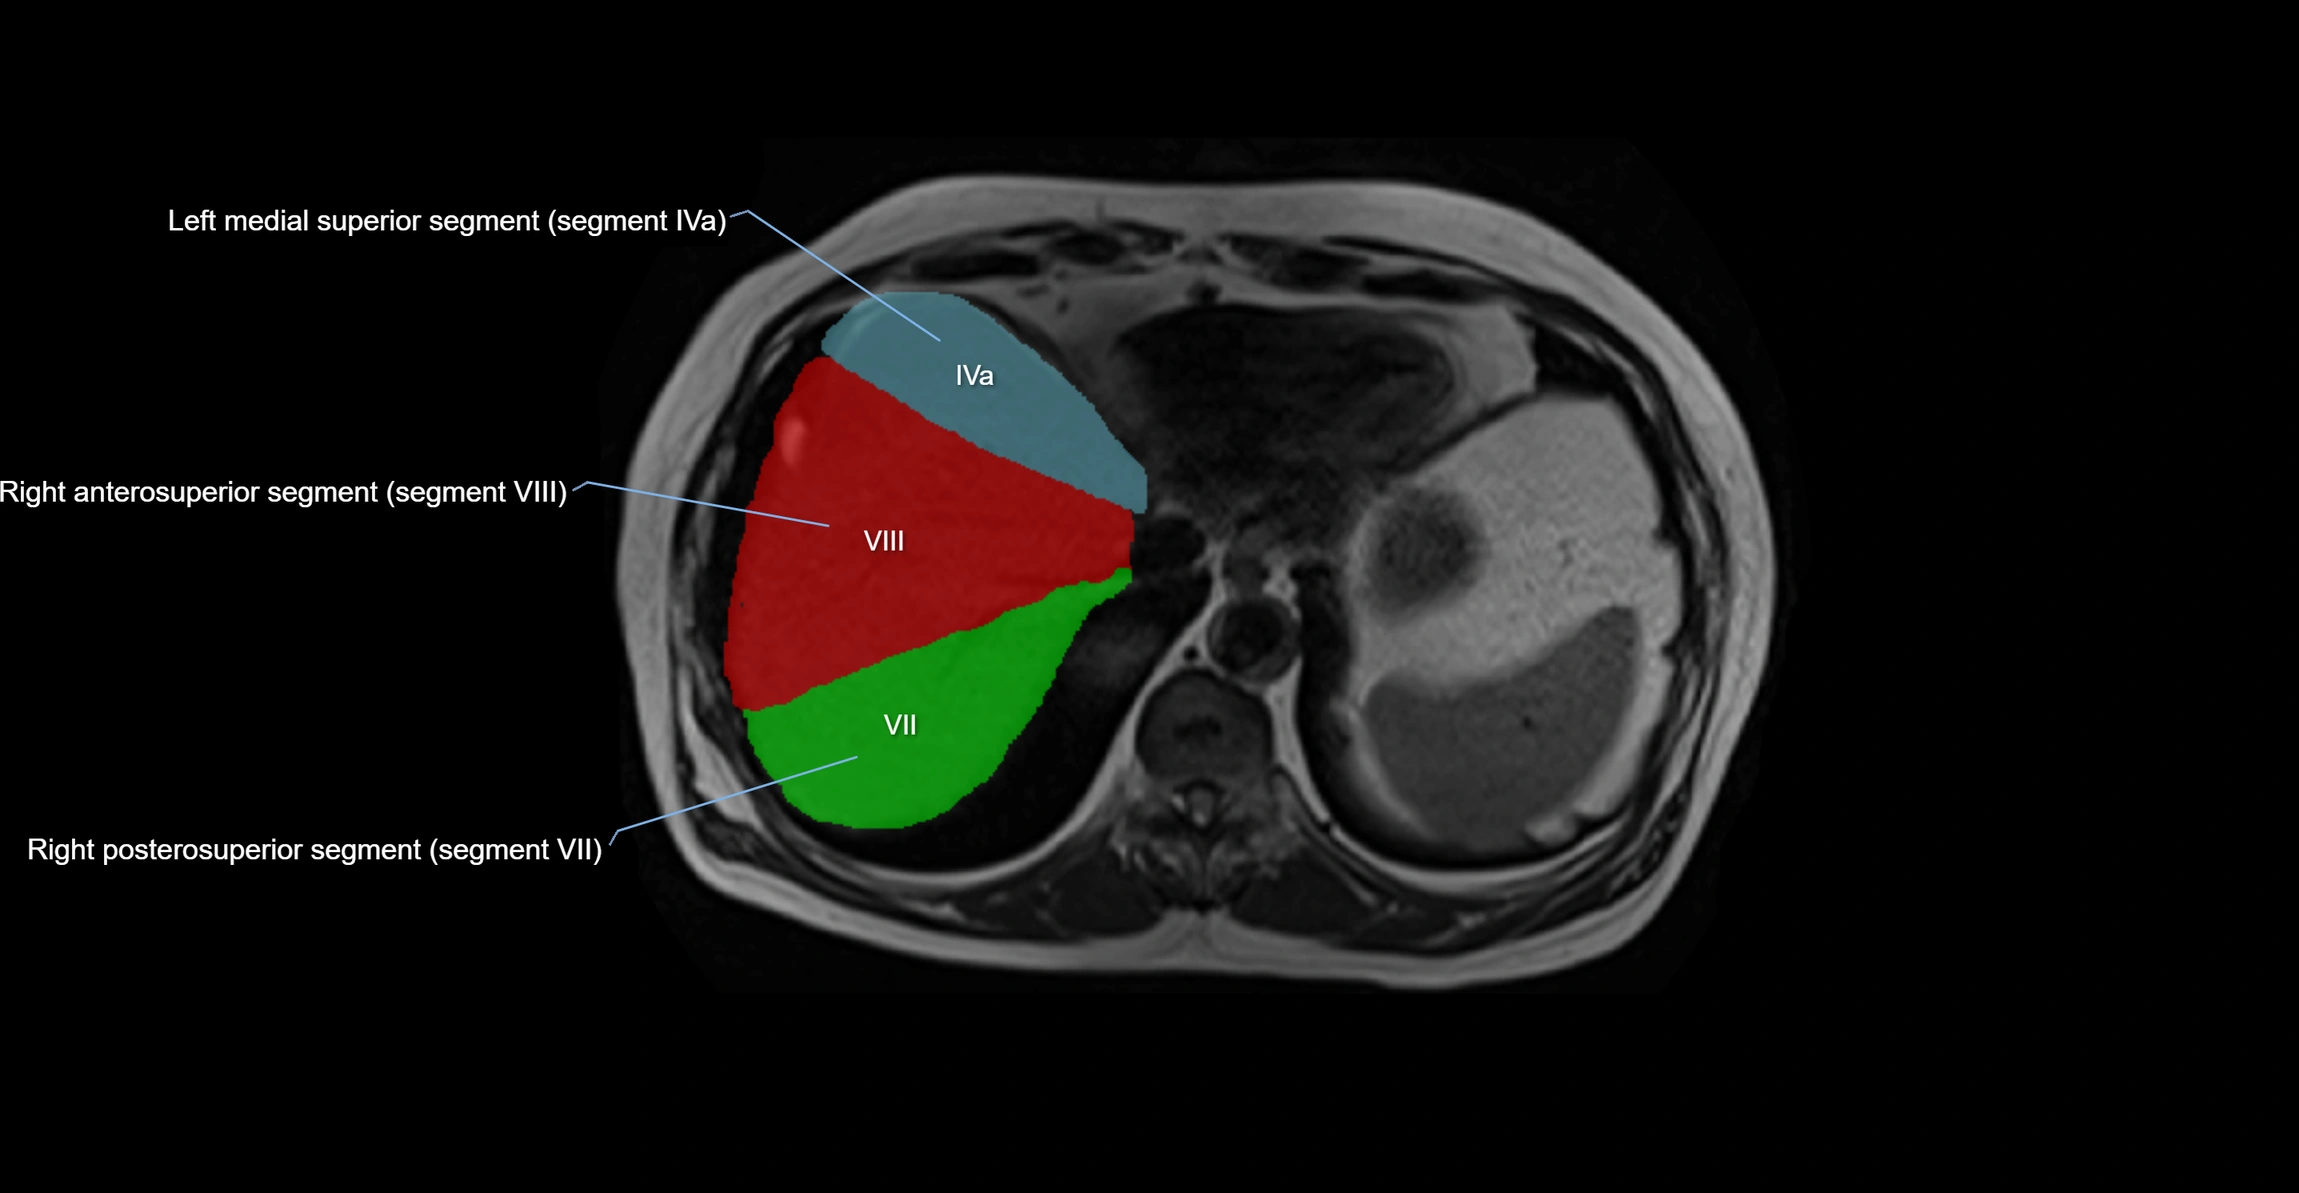

MRI image

image